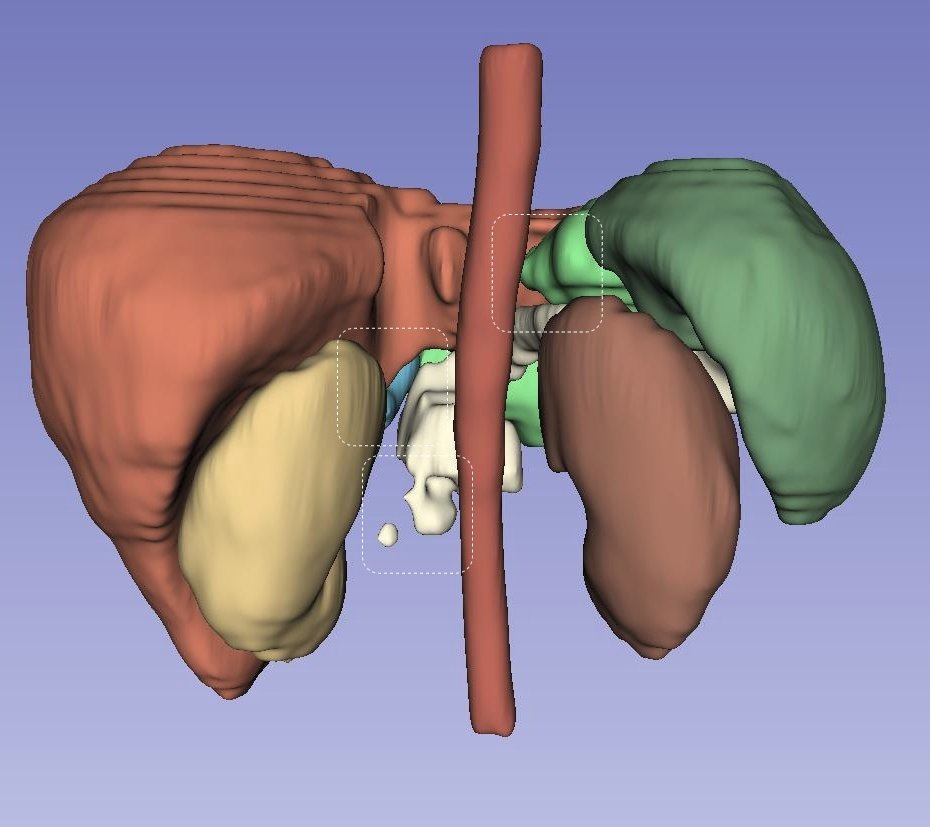

Left Atrial Dataset (LA): Figure˜5 presents a qualitative, three-dimensional visualization of various models’ performance in segmenting the Left Atrial dataset for individual patients. Each row in the figure is dedicated to the segmentation results from a single patient’s dataset, visually assessing each model’s predictive capabilities. In the case of the first patient, shown in the top row, all models except UNETR manage to generate a single entity segmentation, highlighting their ability to integrate disparate anatomical features into a unified model prediction. However, a common challenge across all models is the accurate segmentation of the right corner of the atrium, suggesting a shared area of potential improvement. For the second patient, delineated in the second row, it is discernible that competing models struggle to accurately segment the entirety of the ground truth, resulting in multiple segmented instances rather than a single cohesive structure. Contrarily, LHU-Net succeeds in rendering a single, contiguous segmentation that closely resembles the ground truth, demonstrating its ability to produce smoother and more coherent segmentations. The last patient, as illustrated in the bottom row, presents a challenging case where all models exhibit a tendency for over-segmentation at the base of the atrium. This is indicative of the intrinsic complexity of accurately delineating this anatomical region. Nevertheless, it is worth noting that certain models, specifically UNETR and SwinUNETR-V2, additionally exhibit under-segmentation in other areas, further complicating the segmentation task. In summation, the visualizations in Figure˜5 suggest that LHU-Net consistently generates more robust and smoother segmentations, avoiding the creation of extraneous entities.

NIH pancreas dataset (CT-82): Figure˜6 provides a three-dimensional visualization for the qualitative analysis of pancreatic segmentation across several state-of-the-art models. Each row visually represents the segmentation results from an individual patient’s dataset, offering insight into the predictive precision of each model. For the first patient, illustrated in the first row, it is observable that all models, except for LHU-Net, UNETR++, and SwinUNETR-v2, could not produce a singular, cohesive entity representing the organ. UNETR++ generates a single entity; however, it significantly under-segments the pancreas, failing to capture the complete anatomical structure. In stark contrast, LHU-Net achieves a segmentation that closely approximates the ground truth, underscoring its capability to preserve the organ’s integrity in the segmentation process. The second patient’s data, depicted in the second row, further accentuates the proficiency of LHU-Net in producing a smooth and robust segmentation, particularly when compared to its counterparts. Notably, UNETR++ exhibits a fragmentation in the segmentation, resulting in multiple entities and suggesting a lack of robustness within this dataset. The visualization of the third patient, in the third row, reveals the intrinsic challenges posed by this dataset, as all models predict multiple entities. Nonetheless, LHU-Net distinguishes itself by accurately segmenting the predominant portion that aligns with the ground truth and generating only a minor secondary entity. This contrasts with the other models, which produce multiple, larger erroneous segments, thus compromising the segmentation’s fidelity. Overall, LHU-Net demonstrates superior robustness and smoothness in its segmentation outputs, consistently predicting the pancreas with a higher degree of anatomical accuracy.